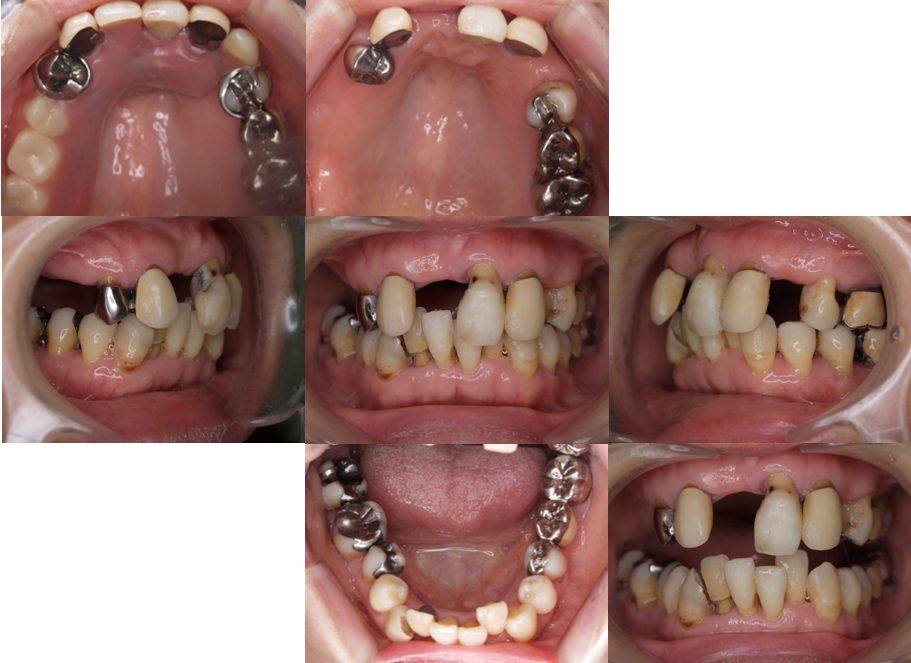

| 主訴 | 50代男性 右上の歯と歯茎が痛い。どこで噛んでいいのか分からないので夜も眠れない |

| 治療内容 | 外科矯正治療・インプラント治療・セラミック治療を行いました。 |

| 治療費 | 4,500,000円(税込み) |

| 治療期間 | 4年(矯正治療期間 3年) |

| 治療回数 | 60回 |

| 想定されたリスク | 顎骨の変形があったので、全身麻酔下による外科処置が必要になり、身体的、精神的負担が増す可能性がありました。 清掃状況によっては矯正中にむし歯が発生するリスクがありました。 |